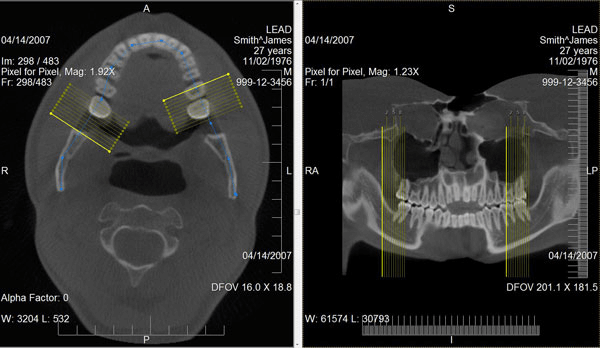

leadtools medical imaging很多年来都是世界第一的医学影像和dicom控件开发包。它提供了完整的dicom数据集、通信和安全支持、医学相关的影像处理和显示、3d重建和高级pac服务器、客户端和影像工作站的组件。同时支持hl7(health level seven卫生信息传输标准)。

使用leadtools medical imaging开发包,可以帮助医疗领域软件开发人员、医疗器械设备厂商、医院构建一个完整的pacs系统,通过成熟的开发接口和已经完成的pacs framework框架,极大的简化开发过程、节省成本,让原本复杂的技术变得简单,开发人员完全可以专注于医院业务,而不需要去研究复杂的通讯标准,因为这一切leadtools都已经帮您做好了。

leadtools 为医学影像开发人员提供了一整套2d切片和3d重建技术,如mri和ct栈,而且提供了5种不同的3d重建技术:mpr、vrt、mip、minip和ssd。全面支持裁剪、缩放、变焦、视角控制、透明度、灰度、投影、测量、标注。您可以很容易的从任意的2d切片图像构建3d模型。而这一切在web端仍然可用。只需要简单的几行代码,拖拽一个控件就可以实现非常强大的3d重建功能。

leadtools dicom 技术使开发人员可以轻松的创建dicom应用程序,包括dicom目录(dicomdir)、通信、安全、影像的显示(2d、3d)和处理(图像测量、标注)。同时也支持modality worklist(mwl scu),当病人需要检查时只需要门诊发送mwl请求,放射科室核查无误后进行检查,并支持mpps,这样pacs可以实时查询病人的检查状态。